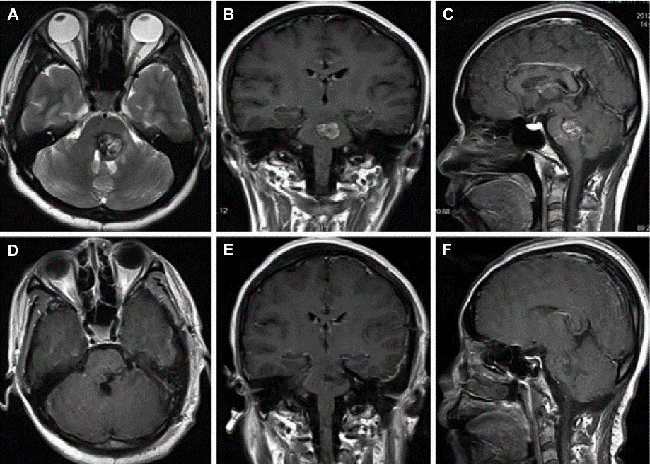

从MRI磁共振T2像特征来看,它确实跟“爆米花”很像。医学上描述其影像表现为:低信号环(陈旧性出血)围绕的混杂信号(不同程度出血呈现出的环瓣)团块。

颅内海绵状血管瘤MRI影像

生长在脑干脑桥部位的海绵状血管瘤MRI影像